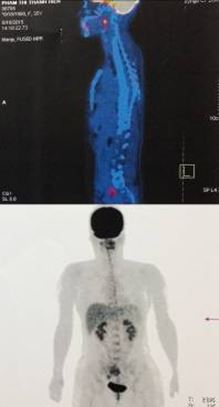

Bệnh nhân được chụp PET/CT đánh giá sau điều trị: Không thấy hình ảnh tăng hấp thu FDG bất thường.

Hình 9: Hình ảnh PET/CT đánh giá sau điều trị: Không thấy hình ảnh tăng hấp thu FDG bất thường trên cơ thể.